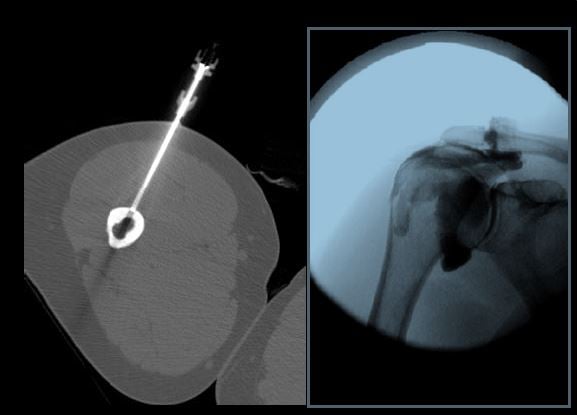

- To train fellows to become efficient, practical, and skilled in the multi-modality imaging of rheumatologic disease and sports related injuries including conventional radiography, CT, arthography, ultrasound and MRI.

- To train fellows to become proficient in orthopedic oncologic imaging including conventional radiography, ultrasound, CT, and MRI.

- To train fellows to become skilled in the selection, performance and interpretation of image guided intervention including fluoroscopy, CT and ultrasound guided musculoskeletal therapeutic procedures including fenestrations and steroid injections.

A wide range of diagnostic services including radiography, US, CT, MRI, and arthrography are complemented by an active MSK interventional service providing diagnostic arthrography, joint injections, and bone and soft tissue biopsies.